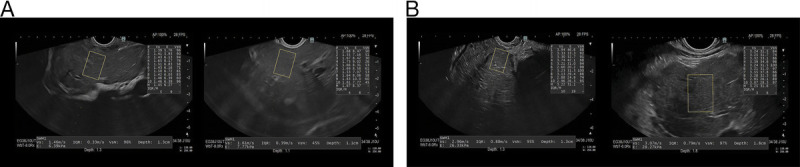

Background and objectives: Chronic liver inflammation leads to fibrosis and cirrhosis. To avoid portal hypertension-related complications, fibrosis' early detection is imperative. Biopsy remains the gold standard, but magnetic resonance elastography (MRE) and EUS-guided elastography are noninvasive procedures currently used for liver stiffness measurement (LSM). Two-dimensional EUS-guided shear-wave elastography (EUS-SWE) represents a more-every-day used technique.The aim of this study is to correlate LSM determined by vibration-controlled transient elastography (VCTE) and EUS-SWE and determine the measurements' accuracy in diagnosing cirrhosis.

Methods: A single-center, nested case-control study was performed between March 2020 and November 2021. Patients were classified into 2 study groups: the cirrhosis group and the control group. Patients from both groups underwent VCTE and EUS-SWE for LSM. A P value < 0.05 was considered statistically significant.

Results: Of the 59 participants included (mean age 63.5 years; 71.1% female), 29 had cirrhosis (49.15%) and 30 were controls (50.84%). In cirrhosis patients, liver fibrosis (F) was staged as F3-4 by VCTE in 82.8%, with a median LSM of 17.8 kPa; through EUS-SWE, 27 kPa in the right hepatic lobe (RHL) and 25 kPa in the left hepatic lobe (LHL). Controls fibrosis was staged as F0-2 by VCTE in 30/30 (100%), with a median LSM of 4.6 kPa (P < 0.001); through EUS-SWE, 5.6 kPa in the RHL (P < 0.001) and 6.5 kPa in the LHL (P < 0.001). The observed agreement was 91.5% for VCTE, 93.2% for RHL-EUS-SWE, and 96.6% for LHL-EUS-SWE. The AUROCs for EUS-SWE and VCTE were over 0.95.

Conclusions: VCTE and EUS-SWE are comparable techniques for diagnosing cirrhosis; however, EUS-SWE had a higher agreement than VCTE, especially in LHL assessment.